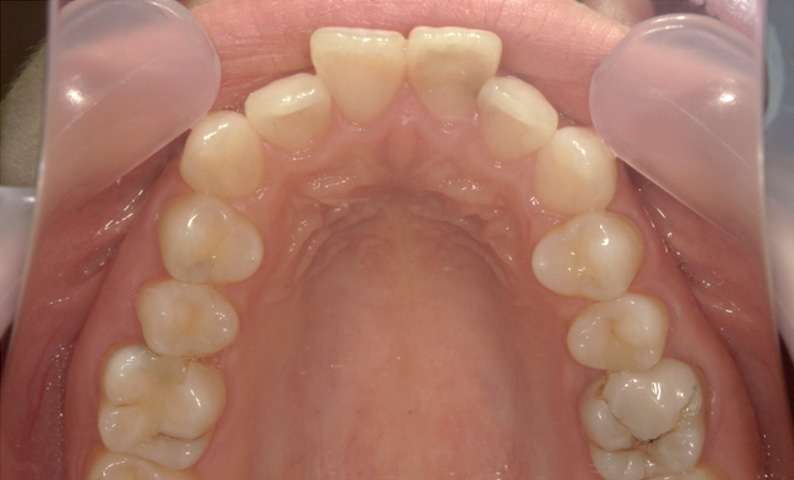

症例_001 「出っ歯」症例

治療期間:13ヶ月金額:54万円+税20代女性出っ歯捻転歯

| Before | After |

|---|---|

|